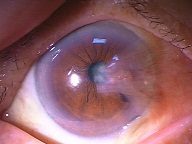

今日いらした24歳女性の症例です。

強い充血を認めます。写真の右側は、はやり目に特徴的な後遺症で、黒目(角膜)が濁っている写真です。もう少し分かりやすい、ヒドイ症例の写真を出したいのですが、ヒドイ症例は第一診察室には入らないようにしていただいたり、写真をとるなどの、余分な時間を少しでも省いて診療を行い、院内感染を予防する必要があり、なかなか難しいのです。